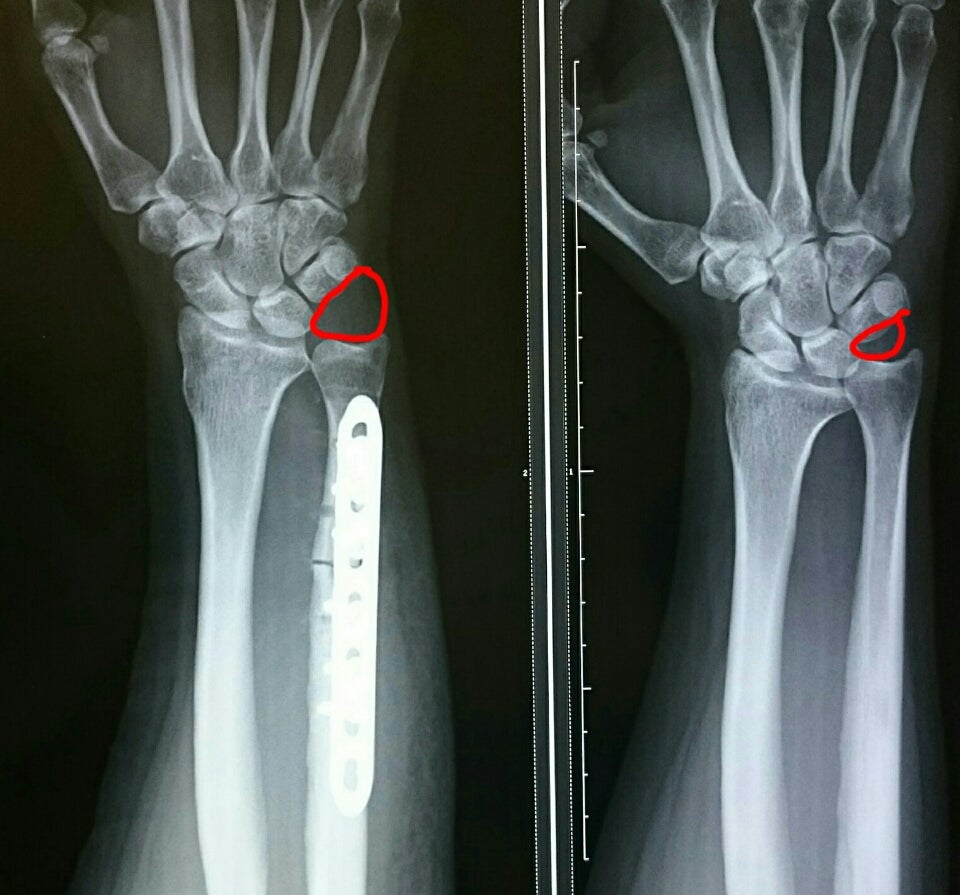

手首がいたい、手首の小指側が痛い、手首を曲げると痛い、尺骨突き上げ症候群。

TFCC損傷尺骨突き上げ症候群druj不安定症入院手術尺骨短縮術ギプス手術跡レントゲン入院記録抜釘手術。